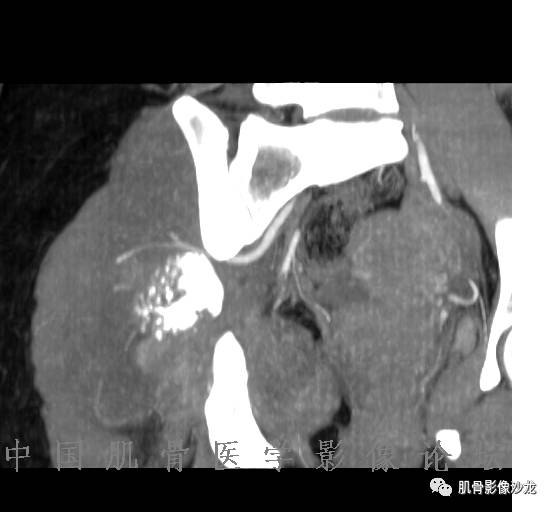

雪舞 :第二例,位于骶骨,有骨质破坏并有软组织肿块,软组织肿块边界清

雪舞: 第二例我们能够看到破坏与软组织肿块不成比例,软组织肿块大,破坏小

雪舞 :第二例挺难的,骨质破坏是溶骨性的,局部皮质中断,软组织肿块外缘光滑